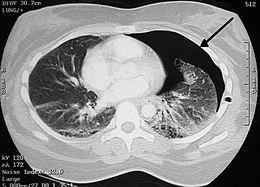

Image from a computed tomography (CT) scan of the chest. On the right (left side of the patient) there is a black area suggesting free air inside the chest

CT scan of the chest showing a pneumothorax on the person's right side. A chest tube is in place (small black mark on the right side of the image), the air-filled pleural cavity (black) and ribs (white) can be seen. The heart can be seen in the center.